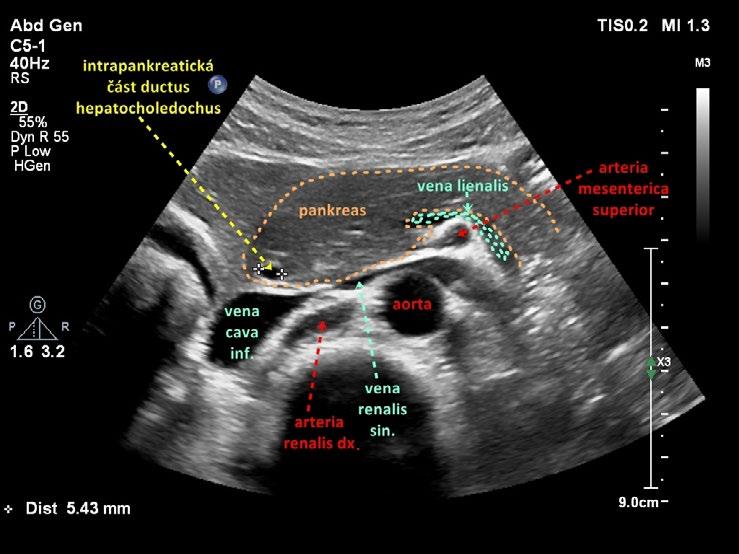

Obr. 1.24 Intrapankreatická část ductus hepatocholedochus

Obr. 1.26 Intrapankreatická část ductus hepatocholedochus podélně